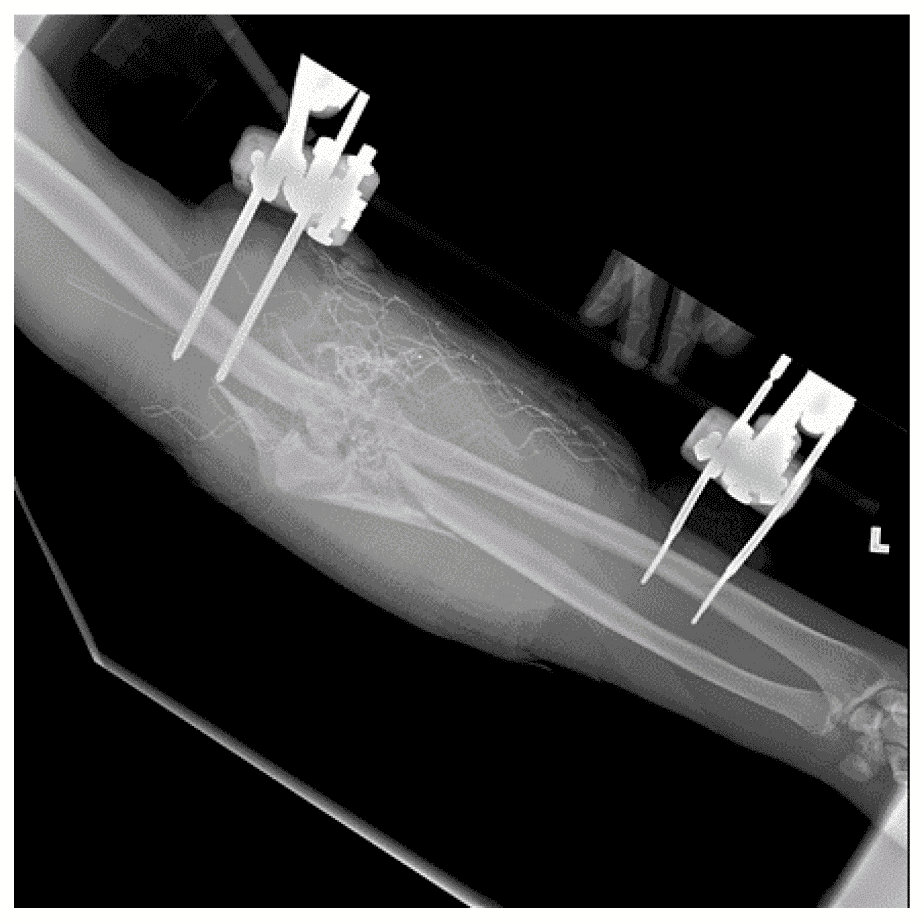

Якщо довжини штанги не вистачає для покриття всієї ділянки перелому, для досягнення бажаної довжини можна з’єднати 2 штанги за допомогою замка «штанга-штанга». Загальна мета будь-якої конструкції полягає у відновленні довжини та загального вирівнювання кінцівки шляхом забезпечення тимчасової репозиції перелому (таким чином покращуючи стабільність), зменшення внутрішньокомпартментного об’єму для забезпечення тампонади кровотечі та відновлення судинного кровотоку шляхом «випрямлення» судин. Якщо немає рентгеноскопії, для початкової стабілізації достатньо простої поздовжньої тракції одночасно із приблизним вирівнюванням у корональній і сагітальній площині. При фіксації колінного суглоба фіксатор слід затягнути із забезпеченням легкої флексії коліна. (Див. Зобр. 1 нижче).

Зобр. 1. Апарат зовнішньої фіксації над колінним суглобом

Зображення 5. Використання апарата зовнішньої фіксації для стабілізації нижньої кінцівки після вибухової травми

На базовій рентгенограмі, отриманій перед процедурою, видно осколкові переломи у дистальній третині стегнової кістки та середній ділянці тіла великогомілкової кістки. Над колінним суглобом було розташовано апарат зовнішньої фіксації, тоді як розширений зовнішній фіксатор у вигляді «дельтоподібної рами» використовує замок стержня у проксимальній ділянці великогомілкової кістки для стабілізації сегментарного перелому великогомілкової кістки.

Зобр. 5a. Осколковий перелом дистального відділу стегнової кістки

Зобр. 5b. Переломи середньої ділянки тіла великогомілкової кістки

Зобр. 5c. Зовнішній фіксатор

Зобр. 5d. Зовнішній фіксатор з дельтоподібною рамою